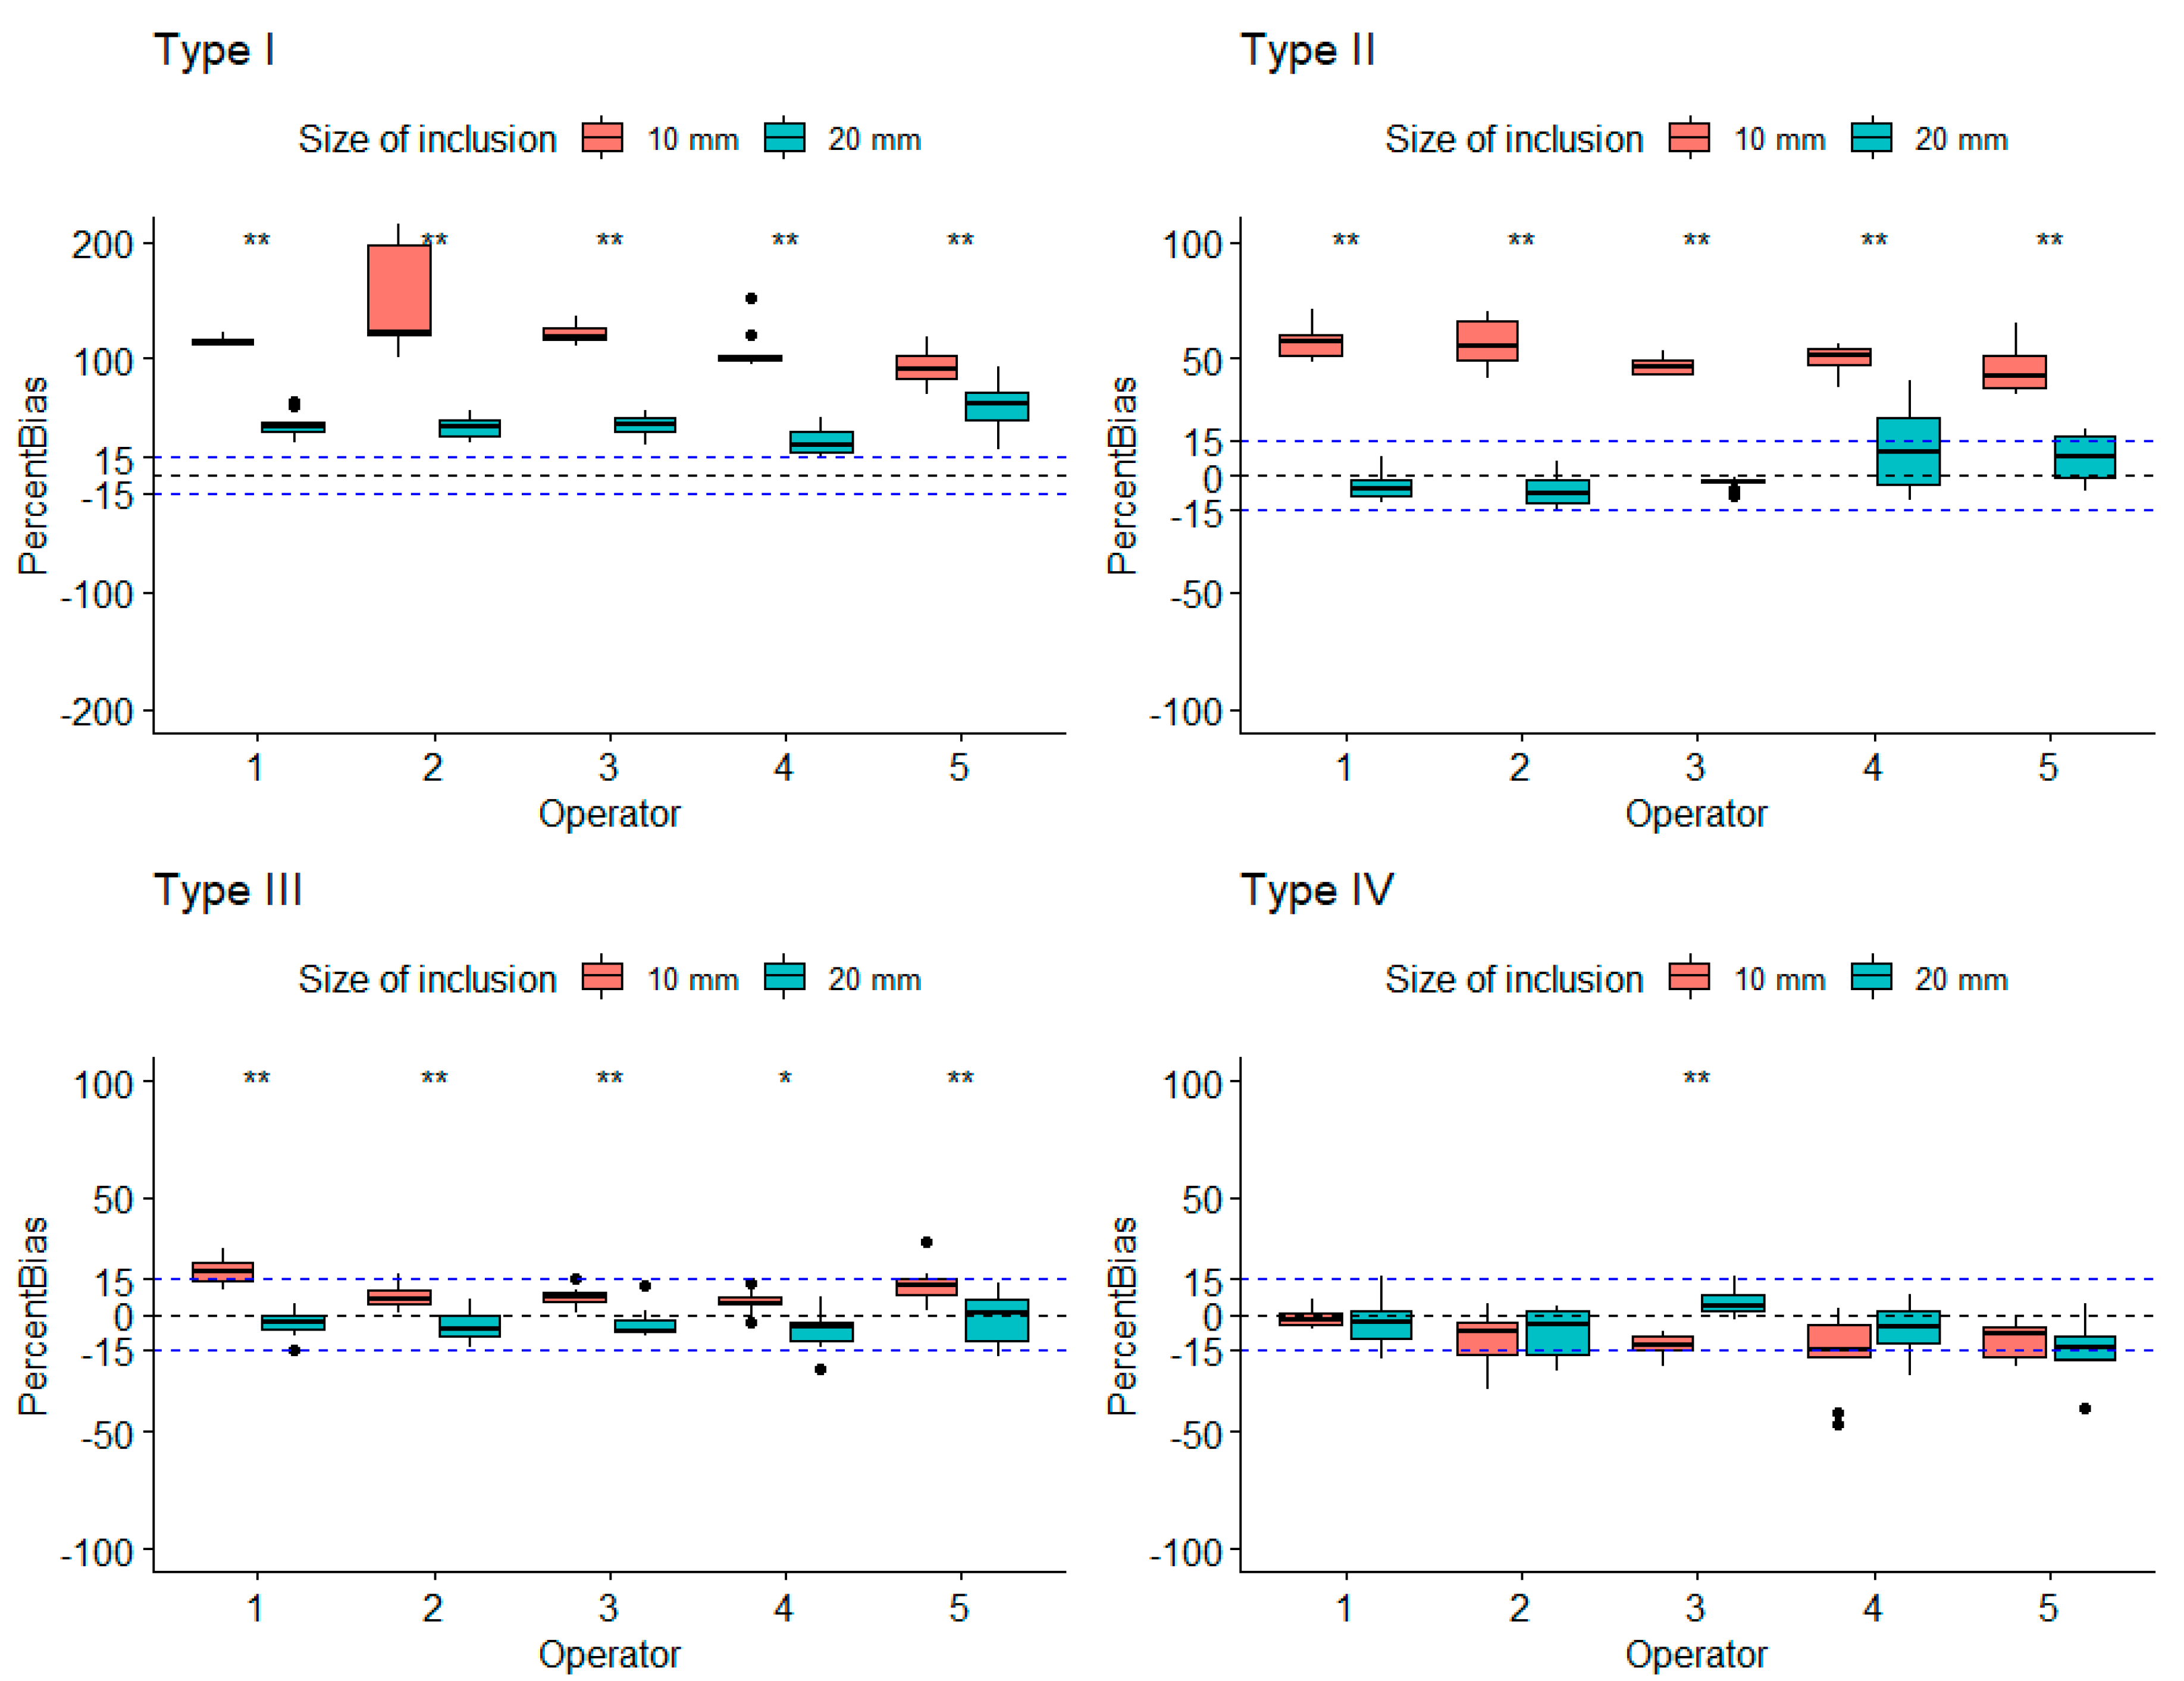

3.1. Robustness Evaluation Regarding Size and Type of Inclusions

3.2. Influence of Depth on Measured Stiffness